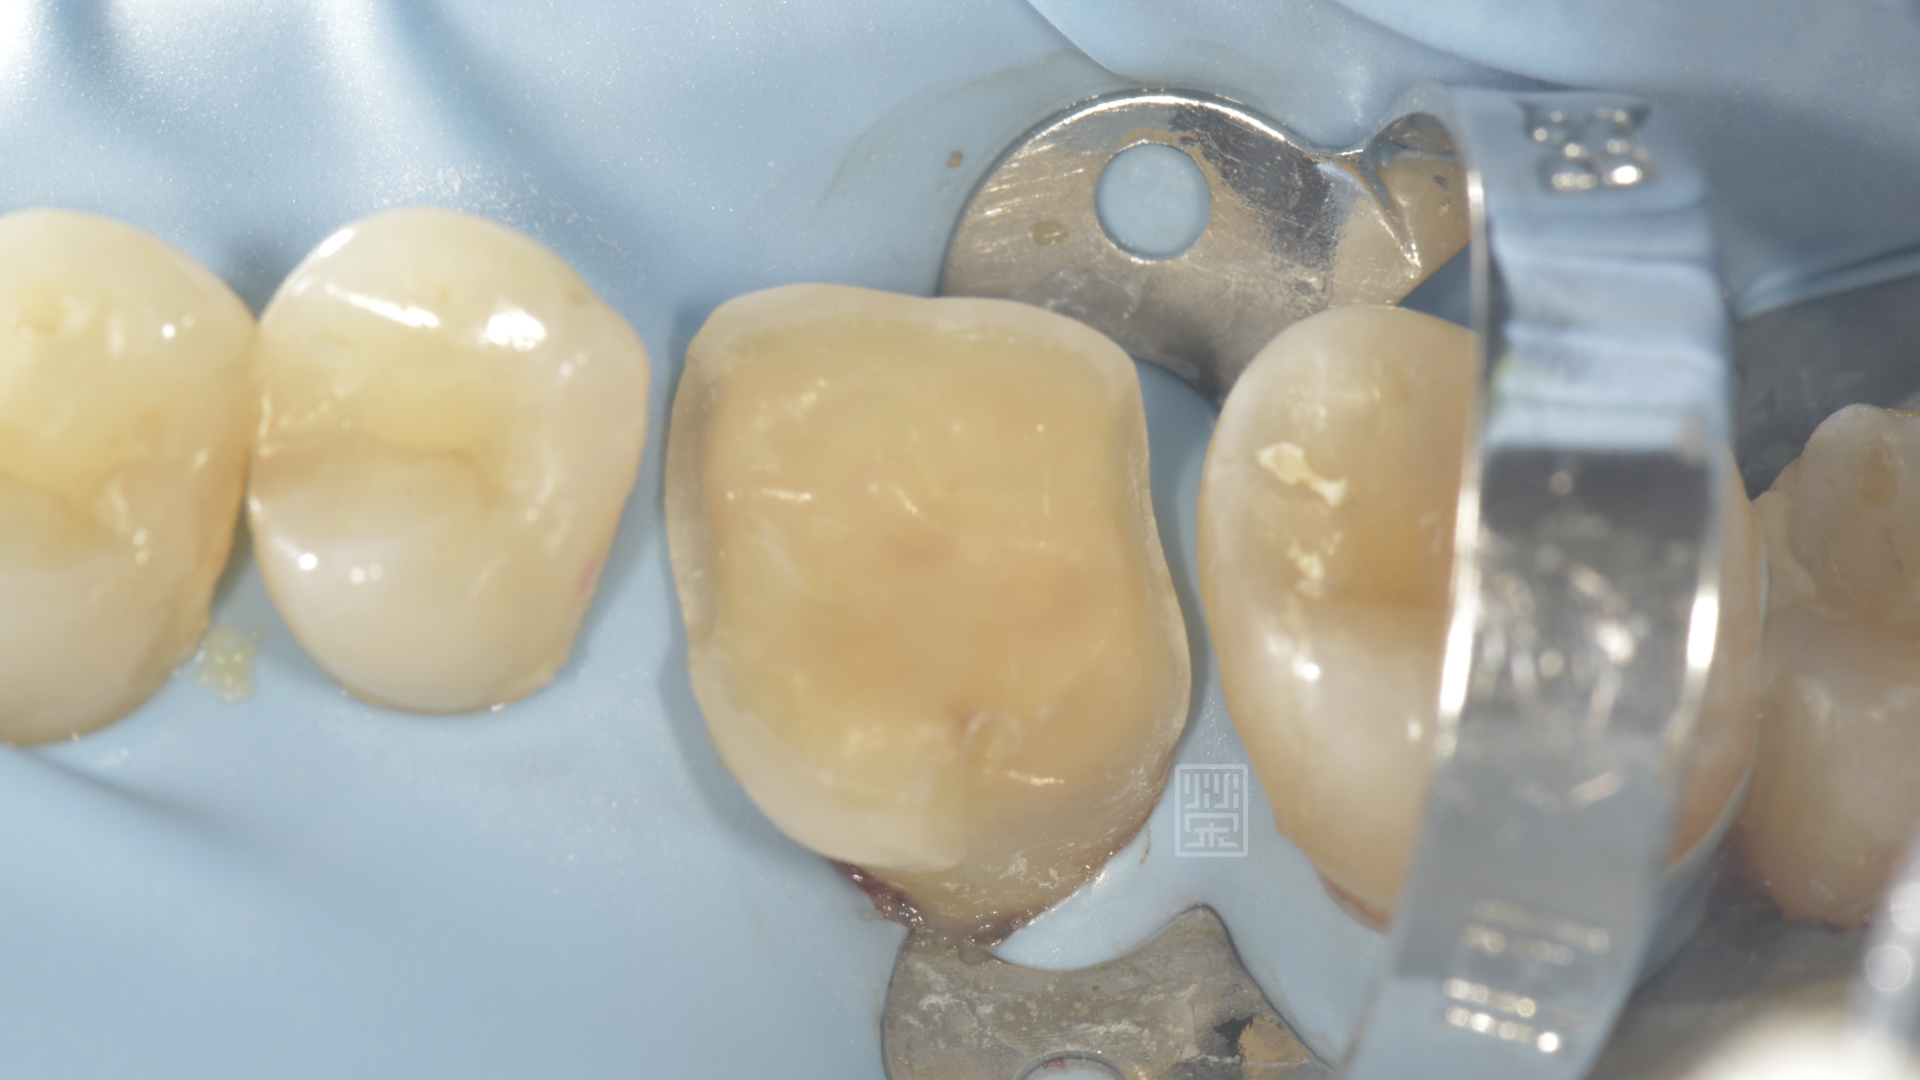

牙冠增長術後將牙齒邊緣獨立出來

牙齒邊緣修行,給全瓷嵌體足夠空間